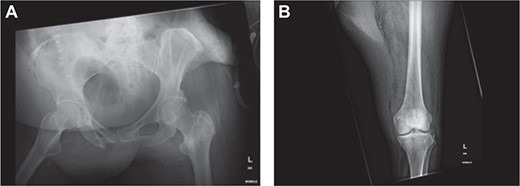

(a) Air in the deep medial and posterior compartments of the thighs and calf suggestive of residual infection in the deep compartment. (b) New finding of air in the right gluteus medius muscle.

Within 14 hours postoperatively, she developed an erythematous patch on her left thigh, and a creatine kinase of 19 000. A bedside finger test was performed which showed dirty dishwater fluid, necrotic fat and lack of bleeding. She was taken to theatre for urgent debridement for suspected NF. Antibiotics were changed to Meropenem, Vancomycin, Lincomycin and Fluconazole. She had extensive debridement of the soft tissue circumferentially on the left thigh, including some muscle. In 10 hours postdebridement, there was a radiological evidence of disease progression with gas in muscle compartments on the lower limb X-rays (Fig. 2a and b), and CT abdomen and lower limbs demonstrating gas throughout the whole left leg and a non-contiguous area in the right gluteal region (Fig. 3a and b). A diagnosis of multi-focal non-contiguous necrotising myositis was made.